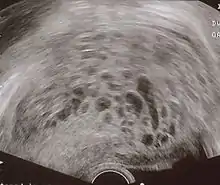

- Transvaginal ultrasonography showing a molar pregnancy.

- Molar pregnancy in ultrasound

The diagnosis is strongly suggested by ultrasound (sonogram), but definitive diagnosis requires histopathological examination. On ultrasound, the mole resembles a bunch of grapes ("cluster of grapes" or "honeycombed uterus" or "snow-storm").[14] There is increased trophoblast proliferation and enlarging of the chorionic villi, and angiogenesis in the trophoblasts is impaired.[15]